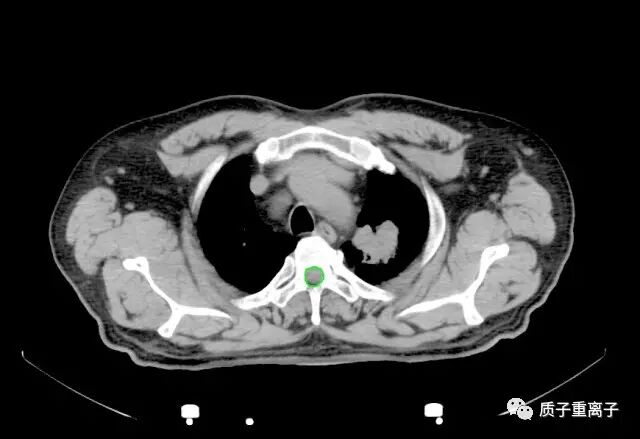

质子治疗前检查图像:左肺上叶见直径3.9cm肿块影;

质子治疗剂量分布:剂量分布良好,对周围正常组织能起到很好的保护,对肿瘤能给予致死剂量: